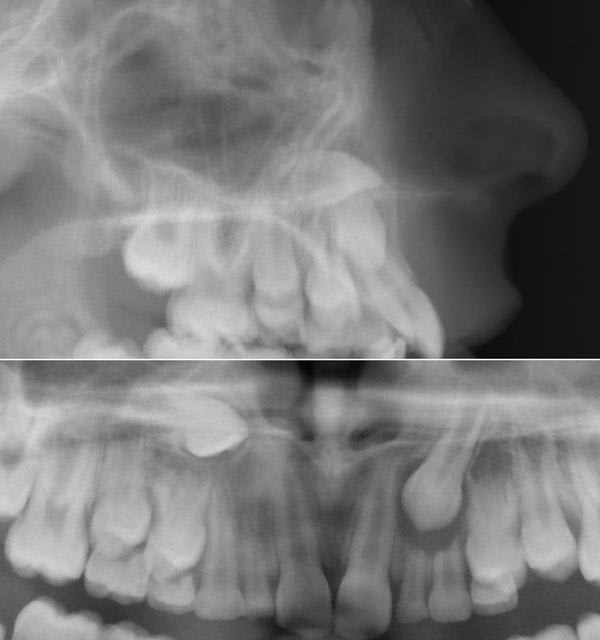

bon alors, sauf erreur on est face à un(e) brachy sévère, qui présente une agénésie des 2 dont la 23 est en train de faire son chemin, dévorant tout ce qui s'oppose à elle (II, III), la 13 a l'air de se plaire dans le palais; tout ceci dans un tableau de cl II 1.

Daniel,quelles sont les moyens que tu vas employer pour aller chercher la 13?et quand le faire?je ne vois pas d'evolution de la racine sur les radios

Au fait, où se trouve-t-elle exactement cette canine ? J’ai dit précédemment qu’un scan n’était pas absolument nécessaire. Si tu intervenais toi-même chirurgicalement, où irais-tu la chercher ?

Eh bien je vois sa cuspide toute proche de la partie inférieure droite de l'orifice piriforme. Peut être la palpe-t-on très haut dans le vestibule?

Je choisirais donc un abord vestibulaire, très haut dans le vestibule, après avoir fait un scanner ou au moins une téléradio de face.C'est vrai, c'est une radio de plus, mais si je devais aller la chercher moi-même, je la ferais.

Tu as bien vu mon cher Roup, elle est effectivement en vestibulaire haute, même si on ne la sent pas à la palpation. Il serait d’ailleurs intéressant que tu expliques aux autres eugénoliens comment tu as raisonné pour la localiser de la sorte.

Pour ce qui est de la position de la canine, la pointe de la cuspide se projette au dessus du plan bi-spinal sur le téléprofil; sur la pano, elle est immédiatement en arrière du bord latéral droit de l'orifice piriforme.

La couronne de cette canine étant supposée ne pas être dans les fosses nasales, elle se trouve donc dans le triangle osseux sur la photo, sous la corticele vestibulaire; c'est ça Dancha?